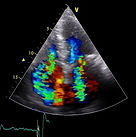

Ecocardiograma

El ecocardiograma es una prueba diagnóstica fundamental porque ofrece una imagen en movimiento del corazón. Mediante ultrasonidos, la ecocardiografía aporta información acerca de la forma, tamaño, función, fuerza del corazón, movimiento y grosor de sus paredes y el funcionamiento de sus válvulas. Además, puede aportar información de la circulación pulmonar y sus presiones, la porción inicial de la aorta y ver si existe líquido alrededor del corazón (derrame pericárdico).